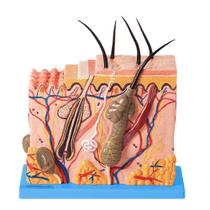

Gente, os modelos anatômicos e simuladores são cópias exatas de diferentes órgãos do corpo de humanos e dos animais, que servem pra professores e outros profissionais mostrarem como funcionam os sistemas do corpo. Eles imitam a estrutura interna e externa do organismo e também são usados pra treinamentos práticos! Quer saber mais sobre eles? Vem comigo que eu te conto:

Gente, os modelos anatômicos e simuladores são cópias exatas de diferentes órgãos do corpo de humanos e dos animais, que servem pra professores e outros profissionais mostrarem como funcionam os sistemas do corpo. Eles imitam a estrutura interna e externa do organismo e também são usados pra treinamentos práticos! Quer saber mais sobre eles? Vem comigo que eu te conto:

- Olha, os modelos anatômicos e simuladores são usados em áreas como Medicina, Enfermagem, Fisioterapia e Veterinária pra imitar órgãos como o coração, rins, útero, olhos, cérebro, as articulações e até o esqueleto inteiro.

- Esses modelos são feitos de resina ou de propiletileno, que é um plástico mais duro, e são desmontáveis, pra apontar todos os detalhes dos órgãos, como camadas, veias e nervos.

- Agora, o simulador pode imitar adultos, idosos e crianças de corpo inteiro ou apenas uma parte dele, como a perna, a cabeça, o pé ou o tronco.

- E tem modelos que vêm com recursos digitais, como programas que reproduzem situações de risco de vida e que indicam quando o procedimento está sendo feito da forma certa. Legal!

Aqui no Magazine Luiza tem vários modelos anatômicos e simuladores. Vem ver!